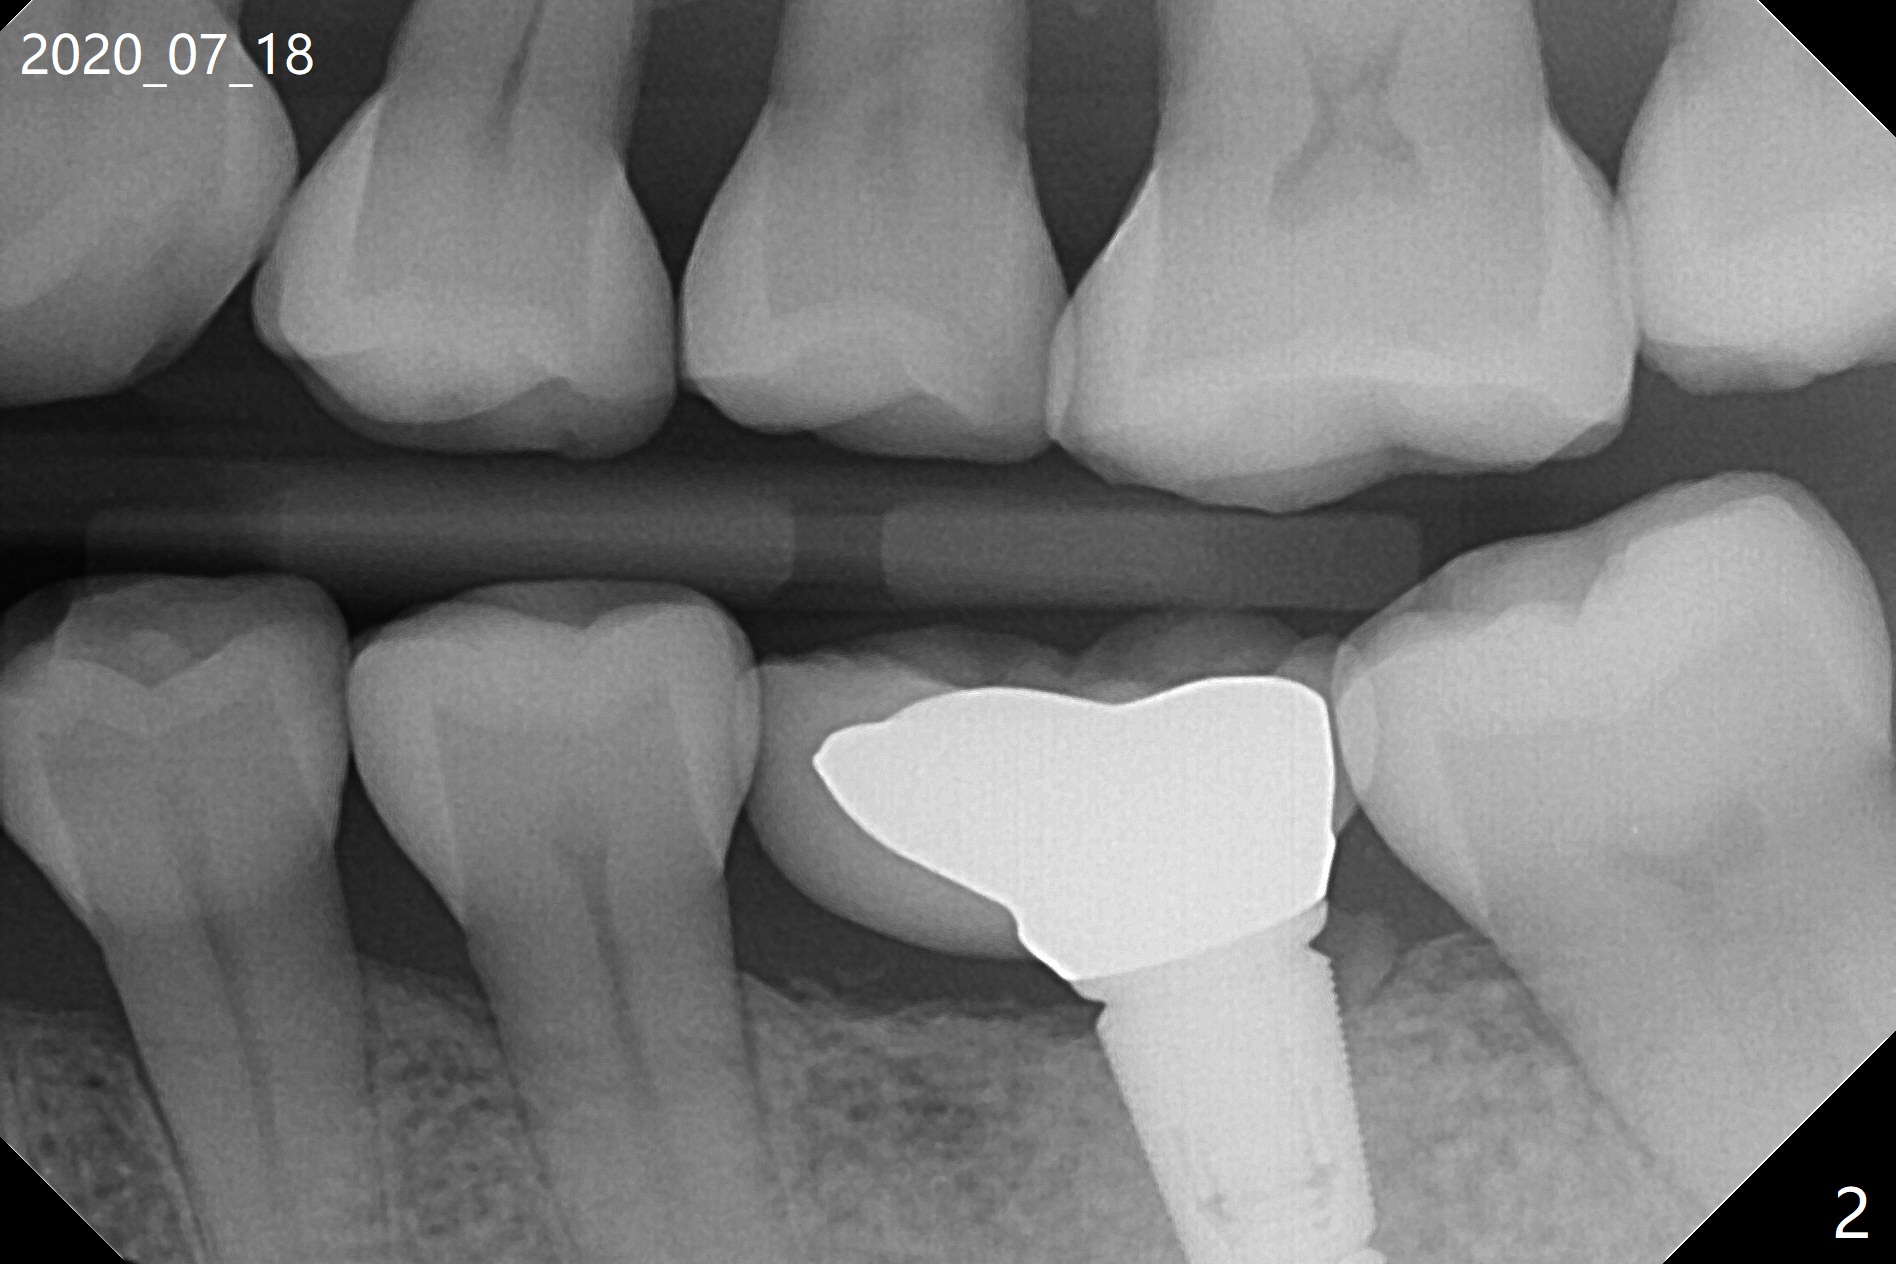

正畸帮助植牙 (互相):1. 缺牙间隙不太窄:先导板植牙后矫正;2.间隙很窄:顺序相反(徒手)